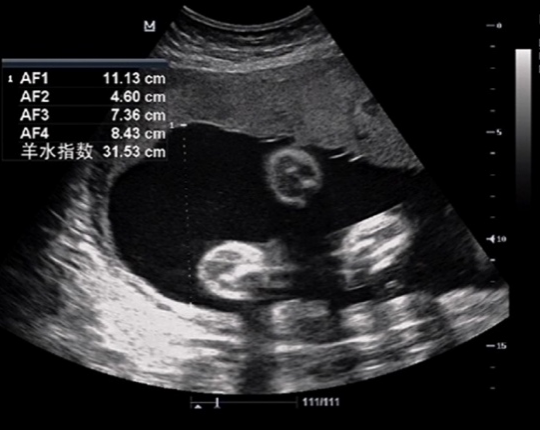

南方医院胎儿医学门诊接诊了一位34岁的孕妇,已妊娠31周余,产检做三级产科超声发现羊水过多、胎儿心包积液。在医生的建议下进行产前诊断,并进行了染色体核型和基因芯片检测,结果提示为:

这意味着胎儿的22号染色体的长臂有一个基因片段缺失,大小约为2.5Mb,即确诊胎儿为22q11.2微缺失综合征。